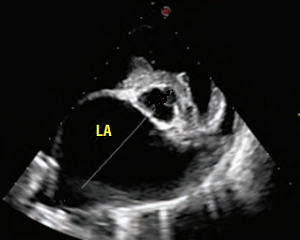

(In the image at right, the red spurt of blood is shooting upward and backward, from the left ventricle, through the not-fully-closed mitral valve, back into the left atrium.)

As noted above, what is not visible outwardly, before the dog reaches heart failure, is enlargement of the left chambers of the heart. As greater quantities of blood leak through the damaged mitral valve from the left ventricle back into the left atrium, the thin-walled atrium gradually begins to swell and enlarge (see x-ray image of a severely enlarged left atrium, outlined in red, above) -- called remodeling or cardiomegaly or dilation -- to accommodate the overload of blood, and there is a reduction in the ability of the left ventricle to provide sufficient blood to meet the demands of the rest of the body. The heart then has to pump harder and faster, to meet those demands. The shut-down of the distant blood vessels also has the effect of causing the left ventricle to beat against a higher resistance, causing another increase in mitral valve leakage.